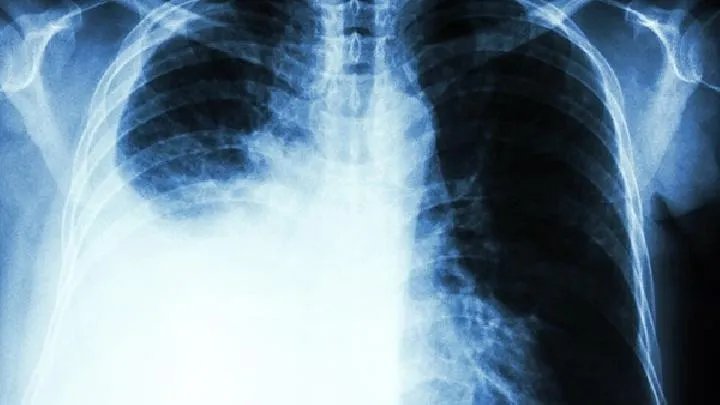

常见的肺纤维化危害1.对循环系统的损坏低氧血症通过化学传感器刺激交感神经。在急性缺氧的早期阶段,由于血管的直接反应和神经反射困惑、心率加速、血压升高、心脏输出增加等,这些都是肺纤维化的危害。心脏输出的增加是化学传感器的即时反应,发现在儿茶酚胺增加之前。随着低氧血症的加重,会发现心律失常,然后血压下降,心率减慢,心脏输出减少。当慢性缺氧时,心脏输出和周围环境的变化并不突出,但肺血管阻力增加,导致右心负荷增加,长期导致慢性肺源性心脏病。2呼吸系统的影响当动脉氧分压降到60mmHg在氧分压下,低氧血症刺激外周感觉器30~40mmHg时起到高峰。呼吸中枢对低氧血症时通气量的反应比二氧化碳为低,这是由于化学感受器对低氧血症的敏感性较差。慢性缺氧时通气量增长。当动脉氧分压突出下降时对呼吸中枢有抑制作用,严重缺氧可导致不规则呼吸和潮式呼吸。这些都是肺纤维化引发的危害,而且缺氧越严重,肺心病出现就越早。长期缺氧会导致机体免疫力下降,容易出现急性呼吸道感染。对神经系统的影响

大脑皮层对缺氧非常敏感。轻度缺氧时,注意力不集中,记忆力下降,定向力减弱。急性缺氧患者可易怒,严重情况下意识模糊,最终昏迷。低氧血症对脑组织的损害包括两个方面:一是缺氧时能量供应不足,导致细胞代谢紊乱、钠泵故障、细胞水肿;严重缺氧会导致细胞酸中毒,pH许多酶不能正常工作,这可能是缺氧后脑水肿的重要因素,对脑组织造成损害。我们都知道肺纤维化的危害!我希望它能对你有所帮助。同时,我也希望您能根据上述介绍对肺纤维化疾病给予足够的重视。如有,应及时到正规医院检查治疗,不要错过最佳治疗期。如果您有任何问题,欢迎咨询我们有问答网络的在线专家。我们将竭诚为您服务。祝你身体健康!